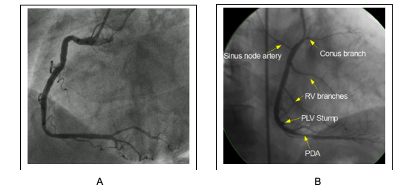

- Các tư thế thường dùng đánh giá ĐMV phải (RCA): hình 7.6

+ Nghiêng trái (LAO 30o): cho phép nhìn toàn bộ ĐMV phải, như hình chữ C và chia 3 đoạn theo góc gập này (hình 7.6A)

+ Nghiêng phải (RAO 30o): cho phép nhìn rõ đoạn 2 ĐMV phải và một số nhánh (hình 7.6B)

Hình 7.6. Hình ảnh chụp ĐMV phải ở tư thế Nghiêng trái 30o (A) và Nghiêng phải 30o (B)